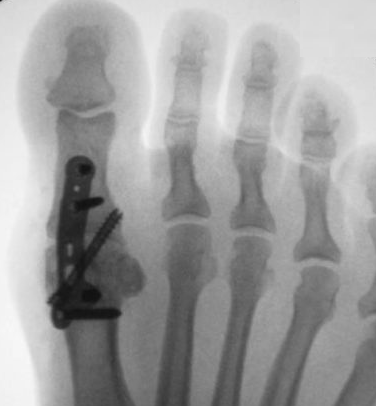

• Quais os dois principais procedimentos cirúrgicos de sacrifício da articulação?

A

• Ressecção de Keller

• Artrodese (padrão ouro)

21

Q

Hálux rígido

• No tratamento cirúrgico de sacrifício da articulação, qual é o padrão ouro de tratamento?

22

• No tratamento cirúrgico, qual a posição ideal para realização da artrodese?

• 15° de valgo +

• Extensão em relação ao solo de 15°

OU

• Extensão em relação ao 1° mtt de 30°